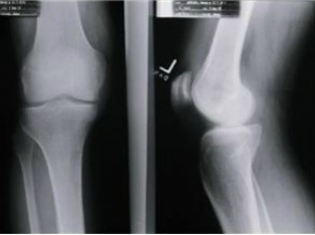

Osteoporosis is characterized by the loss of bone density. It happens when the body does not form enough new bone tissue, which makes bones brittle and prone to fracture. Osteoporosis is most common in menopausal and post-menopausal women.